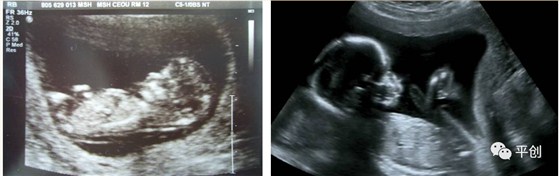

更準確的醫(yī)學診斷,來自B超檢查結(jié)果的輔助,準確的B超檢查結(jié)果,來自B超醫(yī)生看到的B超圖像,清晰的B超成像,來自好的耦合劑。所以說,好的耦合劑對B超的成像很重要。

而影響B(tài)超檢查成像的因素有兩點,一是來自好的探頭,二是來自優(yōu)質(zhì)的耦合劑。如果這兩個產(chǎn)品其中有一個質(zhì)量不過關(guān),即對B超成像有一定程度的影響,可能會有成像不清楚,醫(yī)生無法準確判斷所檢查器官的實際病變,嚴重的有可能度至醫(yī)生誤診的后果。

所生產(chǎn)出來的耦合劑無雜質(zhì)、透明度高、不易干,不化水,易偶合、易擦凈,透聲性超過國家標準的50%(數(shù)據(jù)通過國家指定的第三方檢測機構(gòu)檢測結(jié)果所得),完全地解決了成像不清晰的難題。

安創(chuàng)安必潔耦合劑已經(jīng)在廣東省人民醫(yī)院、南方醫(yī)院、中山大學附屬第一醫(yī)院等全國各三甲醫(yī)院使用,并得到了各醫(yī)院的一致認可,解決了其它品牌耦合劑的偶合性差、透聲功能低,成像不清晰的問題,減少了B超結(jié)果誤診的機率,同時也解決了短期內(nèi)要多次尋找耦合劑品牌的煩惱,所以得到了各合作醫(yī)院的聯(lián)合推薦使用:“好的耦合劑,選用安創(chuàng)安必潔消毒耦合劑”。